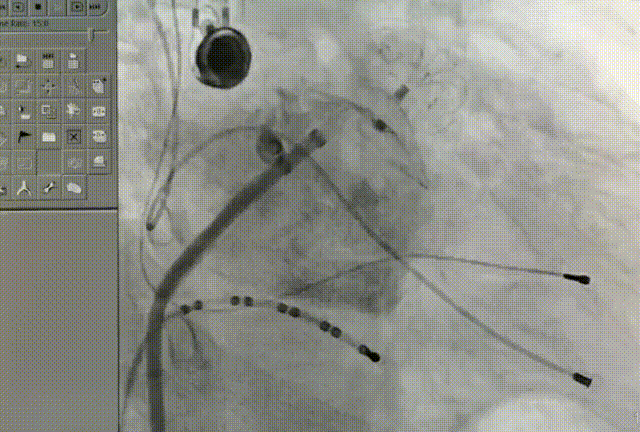

常规肝位造影显示,左心耳锚定区约26mm, 开口约29mm, 因此选择型号为LT-LAA-2834的LAmbre™左心耳封堵器对患者实施封堵。LAmbre™植入过程一步到位,U型钩均完全展开。随后复查造影及TEE结果,封堵盘呈“碗状”形态完美贴合于左心耳口部,无残余分流,牵拉测试稳定,综合评估符合COST原则,随后完美释放,封堵效果理想。术后,患者各项指标正常,身体恢复良好。

封堵器牵拉测试稳定

封堵器释放后头位与肝位造影